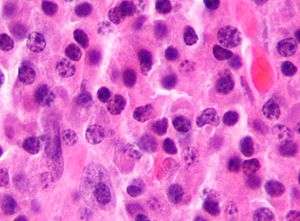

Bone marrow aspirate showing the histologic correlate of multiple myeloma under the microscope. H&E stain.

Cellular morphology

The Plasma cells seen in multiple myeloma have several possible morphologies. Typical of plasma cells, they will usually have an eccentric nuclei. Because they are actively producing antibodies, the Golgi apparatus will typically produce a light-colored area adjacent to the nucleus, called a perinuclear halo. The cells may otherwise have the appearance of a normal plasma cell with a single nucleus and a single nucleoli with vesicular nuclear chromatin. Other common morphologies that are seen include:

- Bizarre cells, which are multi nucleated.

- Mott cells, containing multiple clustered cytoplasmic droplets or other inclusions (sometimes confused with auer rods, commonly seen in myeloid blasts)

- Flame cells, having a fiery red cytoplasm.[23] [24]